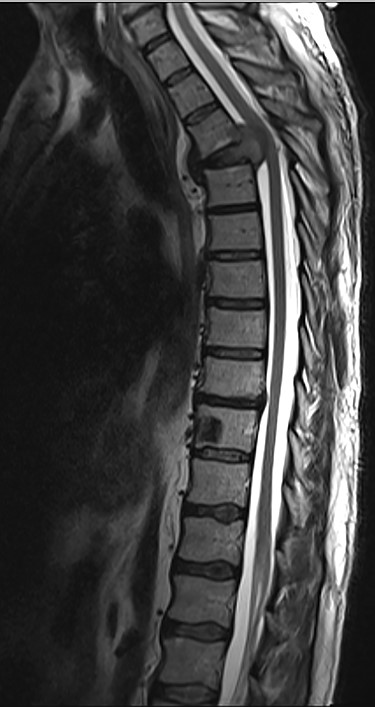

Spinal images are presented in Figs 1–6. Cross-sectional imaging revealed no other neoplastic lesion. He received dexamethasone 10 mg bolus then 4mg four times daily with appropriate proton pump inhibitor coverage. Due to no distinguishable major arterial feeder upon review of the imaging jointly with the neuroradiologist, pre-operative embolization was not attempted. The following morning, he underwent posterolateral right costotransversectomy, ligation of the ipsilateral T4 nerve root, T4 vertebrectomy and insertion of an expandable titanium cage with T1–T7 pedicle screw fixation (Figs 7 and 8). Post-operatively his pain improved to VAS 2/10 and motor power in his left lower limb improved to MRC grade 4/5. The patient was discharged home Day 10 post-admission with physiotherapy.

Sagottal T2W MRI showing synchronous lytic lesions in T10 & L3 vertebral bodies.